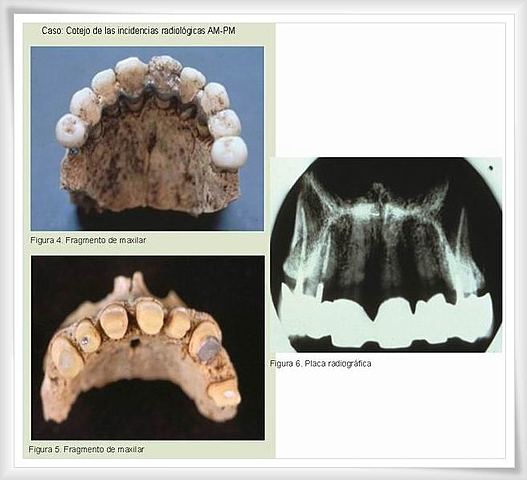

• Sistema Dental/Rayos X

Sistema Dental/Rayos X

Investigadores japoneses desarrollan un sistema dental de combinación de rayos X. Este sistema puede hacer coincidir automáticamente las radiografías dentales en una base de datos, y hace una coincidencia positiva en menos de 4 segundos.